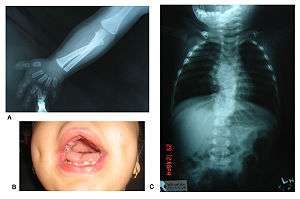

Robinow noted the resemblance of affected patients' faces to that of a fetus, using the term "fetal facies" to describe the appearance of a small face and widely spaced eyes.[1] Clinical features also may include a short, upturned nose, a prominent forehead, and a flat nasal bridge. The upper lip may be "tented,"[1] exposing dental crowding, "tongue tie," or gum hypertrophy.

Though the eyes do not protrude, abnormalities in the lower eyelid may give that impression. Surgery may be necessary if the eyes cannot close fully. In addition, the ears may be set low on the head or have a deformed pinna.

Patients suffer from dwarfism, short lower arms, small feet, and small hands. Fingers and toes may also be abnormally short and laterally or medially bent. The thumb may be displaced and some patients, notably in Turkey, experience ectrodactyly.[1] All patients often suffer from vertebral segmentation abnormalities. Those with the dominant variant have, at most, a single butterfly vertebra.[2] Those with the recessive form, however, may suffer from hemivertebrae, vertebral fusion, and rib anomalies. Some cases resemble Jarcho-Levin syndrome or spondylocostal dysostosis.